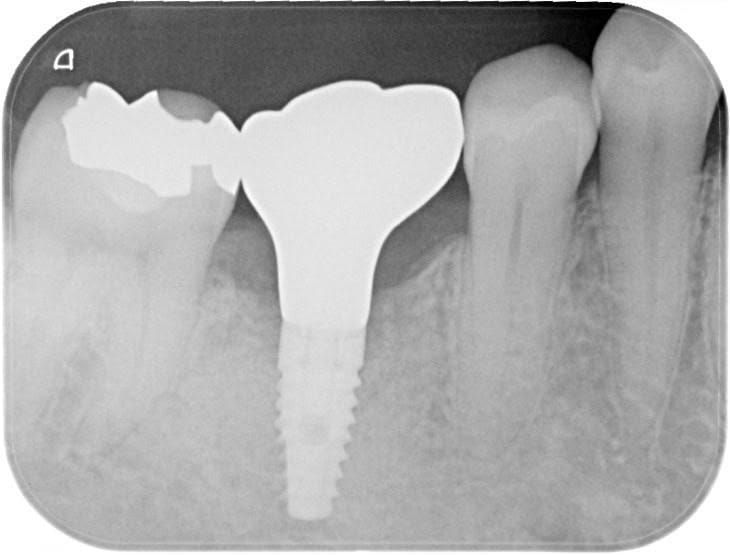

前医でインプラントの埋入角度が悪く、インプラント周囲炎になってしまった患者様の症例です。

インプラントが虫歯になることはありませんが、インプラント周囲炎というインプラントの歯周病にはなります。

インプラント周囲炎の主な原因は汚れ(菌)と力です。このように斜めに埋入されているインプラントは、真っ直ぐ埋入されているものに比べて汚れも溜まりやすく、噛む力も斜めにかかってしまうため、インプラント周囲炎になるリスクが大幅に高くなります。

この患者様は内側の骨が大幅に溶けてしまっていたので、前のインプラントを撤去して、骨を再生させると同時にインプラントを正しい位置と角度で埋入し直しました。溶けてしまっていた骨が治っていることもレントゲンでご確認いただけるかと思います。

インプラントは「どこの位置にどのような角度で入れるか」によって、一生使い続けられるかどうかの期待値が大きく異なります。値段だけを基準にクリニックを決めるのではなく、信用できる歯医医師と治療を進めることをお勧めします。

担当 理事長 佐藤悠野